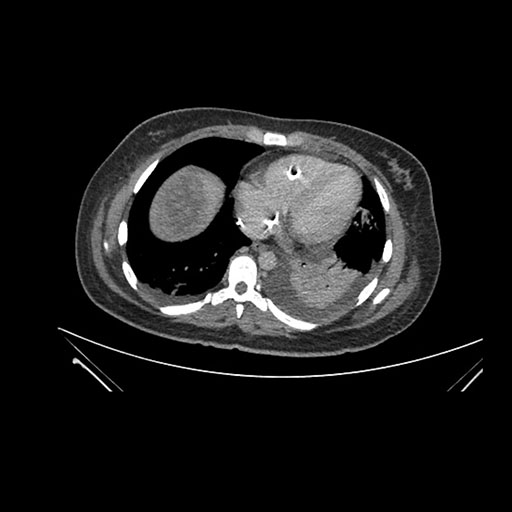

Imaging Analysis

Look through the patient's CT scan to identify any areas of concern for the necessary procedure.

Coronal Arterial

Based on initial findings, which issue(s) would you be most concerned about?